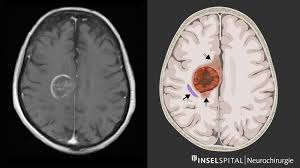

Hirnmetastasen Neurochirurgie Inselspital Bern